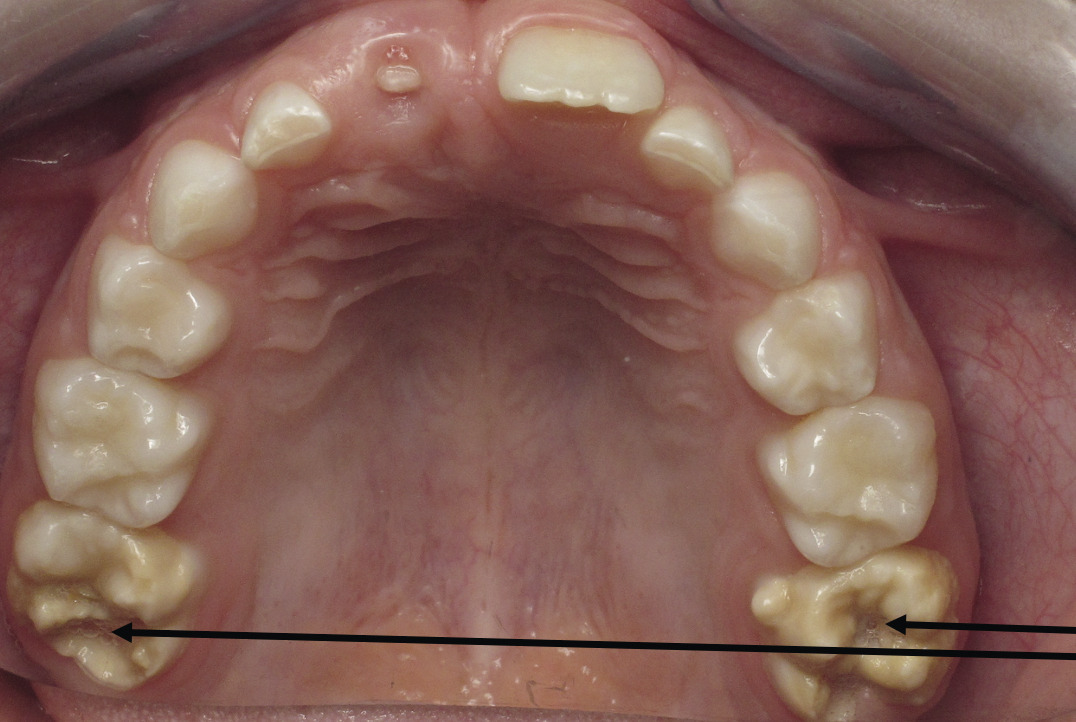

Anomalie de la structure de l’émail, la MIH se traduit par un défaut qualitatif de l’émail sur au moins une des quatre premières molaires permanentes, associé ou non à une atteinte d’une ou plusieurs incisives permanentes (fig. 1 ).1 Les autres dents permanentes sont plus rarement atteintes. On peut également retrouver une atteinte similaire au niveau des deuxièmes molaires temporaires, appelée alors HSPM (hypomineralised second primary molars). Un enfant atteint de HSPM a 5 fois plus de risque d’être atteint de MIH en dentition permanente.

Le diagnostic repose sur l’observation clinique : des opacités (taches) blanches, beiges ou brunes de taille variable sont présentes et visibles sur les dents atteintes (fig. 1, 2 et 3 ). Les opacités, bien démarquées, sont présentes dès l’éruption de la dent et leur taille ne se modifie pas dans le temps. Cependant, l’émail étant plus fragile, des fractures amélaires postéruptives sont observées, entraînant des pertes de substance surtout au niveau des molaires, qui sont soumises aux forces de la mastication. L’atteinte est asymétrique, c’est-à-dire que pour un même patient sa sévérité peut varier d’une dent à l’autre, allant d’une absence d’atteinte à une perte de substance importante, en passant par une dyschromie discrète. Si une tache est observée sur une incisive permanente, il est important d’examiner les molaires permanentes. Le médecin généraliste doit alors évoquer une anomalie de structure dentaire et orienter le patient vers un chirurgien-dentiste. Celui-ci confirmera le diagnostic de MIH ou établira un autre diagnostic. Les diagnostics différentiels sont :